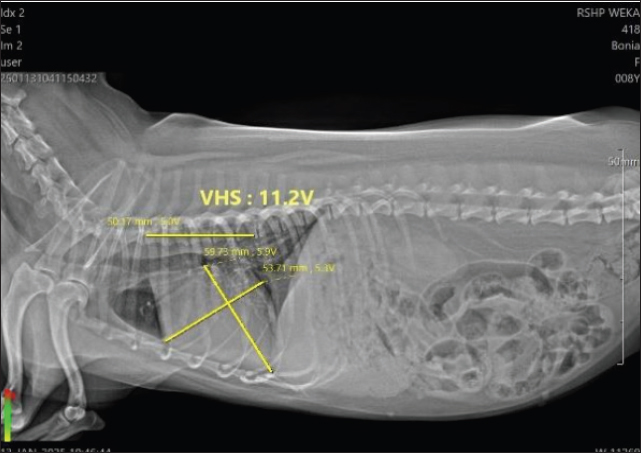

Figure 1 shows the VHS measurement of Bonia’s heart, with a value of 11.2 V, whereas the normal range in dogs is 9.5–10.5 V. This indicates that Bonia is experiencing cardiomegaly. Figure 2 shows the TIHS, a method used to detect MMVD. Under normal conditions, the TIHS value is less than 3 (Marbela et al., 2023); therefore, Bonia is not affected by MMVD.

Fig. 1. VHS 11,2 V of Bonia.

Table 1 shows that each patient presented with different clinical signs and laboratory results. In Table 2, Bonia was reported with hypotension (77/35 mmHg) and a VHS value of 11.2 V, which falls into the cardiomegaly category. The THIS score was 2.9, indicating no evidence of MMVD because the normal THIS value for dogs is below 3 (Lam et al., 2021). Echocardiography in B-mode showed normal valve movement and valve structure, whereas M-mode measurements were within the normal range. However, color Doppler examination revealed turbulence, suggesting disturbed blood flow and valvular regurgitation. Color Doppler function is used to detect congenital or acquired cardiac diseases (Wess et al., 2021). According to the cardiac biomarkers presented in Table 3, Bonia had NT-proBNP levels of 0.5 ng/ml and cTnI levels <0.1 ng/ml. These values are within the normal range, indicating no myocardial damage or cardiac injury.